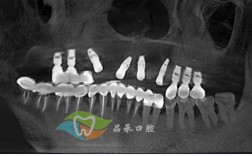

种植牙是通过外科手术将人工牙根(种植体)植入牙槽骨内,待其与骨组织结合后,再安装基台和牙冠,从而恢复牙齿功能的一种修复方式,与传统义齿相比,种植牙具有以下优势:

- 每年至少1次专业复查,通过X光监测骨结合情况。